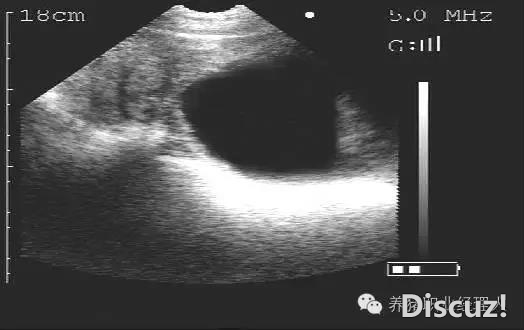

配種母豬不同日齡妊娠B超檢查(圖文并茂,超詳細)

早日發(fā)現(xiàn)空懷母豬,減少非生產(chǎn)天數(shù)帶來的經(jīng)濟損失,B超測孕已經(jīng)成為最普遍的測孕方式。今天,就給大家講解一下B超在現(xiàn)場的使用!正確熟練的使用B超儀,可以準確判斷母豬妊娠情況,減少非妊娠母豬,從而縮短無效飼養(yǎng) ...